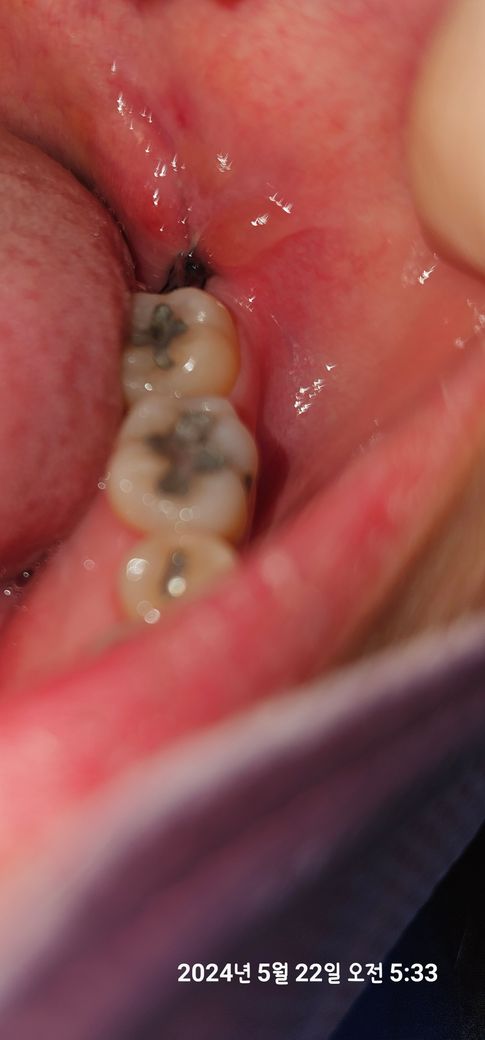

사랑니 발치 후 피덩어리? 그게 무조건 있어야하나요?

잘은 안 보이는데 실이 검은색인지 몰라도 실들만 보이는 것 같아서요

집 와서 자세히 보니 제가 느끼기에는 혈전?은 크게 안 보이고 실밥으로 꿰매진 것만 잘 보여요 검은 실로

• 1번 째 사진

발치 이후에 초기에는 혈병이 있으나 시간이 지나면서 혈병이 사라지고 섬유화 과정을 거칩니다. 현재 사진에서는 정확히 보이지 않아 판단이 어려우나 드라이소켓이라면 단순히 아픈 정도가 상상을 초월합니다. 따라서 대부분 이러한 통증이 아니라면 정상적인 회복으로 보시는 것이 맞으나 너무 걱정이 되신다면 발치한 치과를 방문하여 검사를 하는 것이 좋습니다.